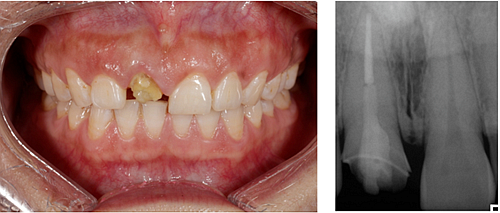

患者右上前牙因外傷冠修復(fù)體脫落來我院找口腔修復(fù)科金小婷醫(yī)師治療。經(jīng)檢查,患者剩余牙體組織少,經(jīng)溝通確認后,進行上前牙全瓷冠修復(fù)。

△臨時牙佩戴